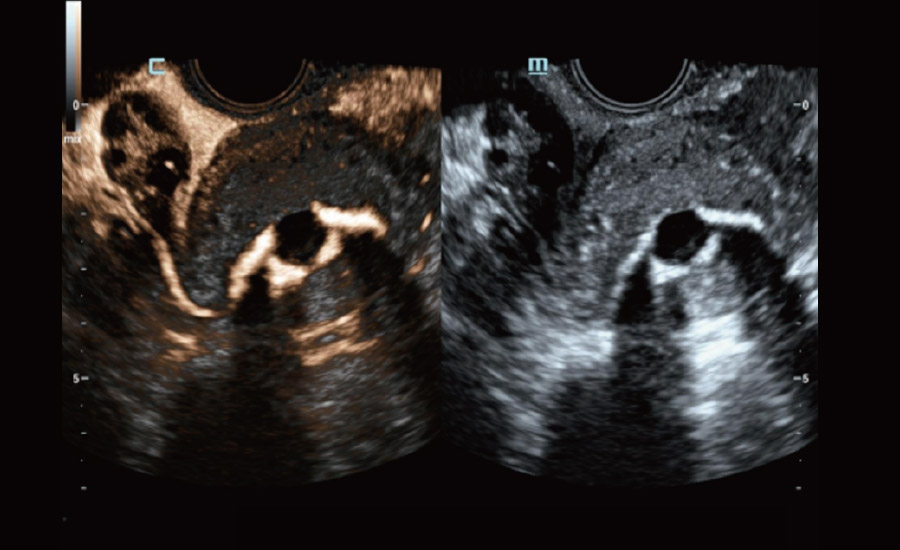

UMA (angiografia ultramicroscĆ³pica)

A tecnologia inovadora elimina as limita??es das tradicionais imagens com Doppler. Com resolu??o espacial e sensibilidade de fluxo ultra-altas, permite a detec??o de perfus?es de fluxos muito sutis e lentos, ampliando assim a aplica??o clĆnica da avalia??o qualitativa e quantitativa do ultrassom no cĆ©rebro fetal, rins, placentas, endomĆ©trios, ovĆ”rios etc.

UMA ā Fluxo renal do feto

UMA ā Fluxo uterino e endometrial